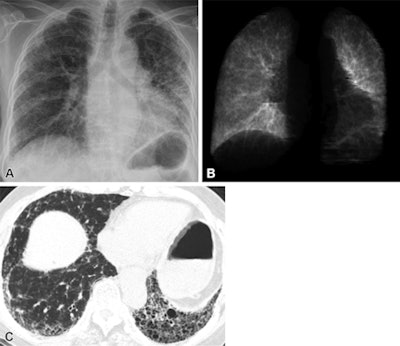

For the study, the investigators first trained a deep-learning model to measure TLC using 50,000 consecutive chest CT scans performed between January 2015 and June 2017 at their institution. They then fine-tuned the algorithm on 3,523 pairs of posteroanterior chest radiographs and plethysmographic TLC measurements from consecutive patients who underwent pulmonary function testing on the same day. To test the model, they used data sets from two tertiary care centers and one from a community hospital that included 217 patients with IPF.

The group found that the difference between TLC on the x-ray images and those estimated by the algorithm were small (0.69 liters vs. 0.73 liters) in the first external test set, and 0.52 liters and 0.53 liters in the second external test set. In the imaging set of 217 patients with IPF, a greater estimated TLC was associated with lower mortality risk (adjusted hazard ratio, 0.97 per percent, p = 0.001), the team found. In the imaging set of 217 patients with IPF, greater estimated TLC percentage was associated with lower mortality risk (adjusted hazard ratio, 0.97 per percent, p = 0.001).